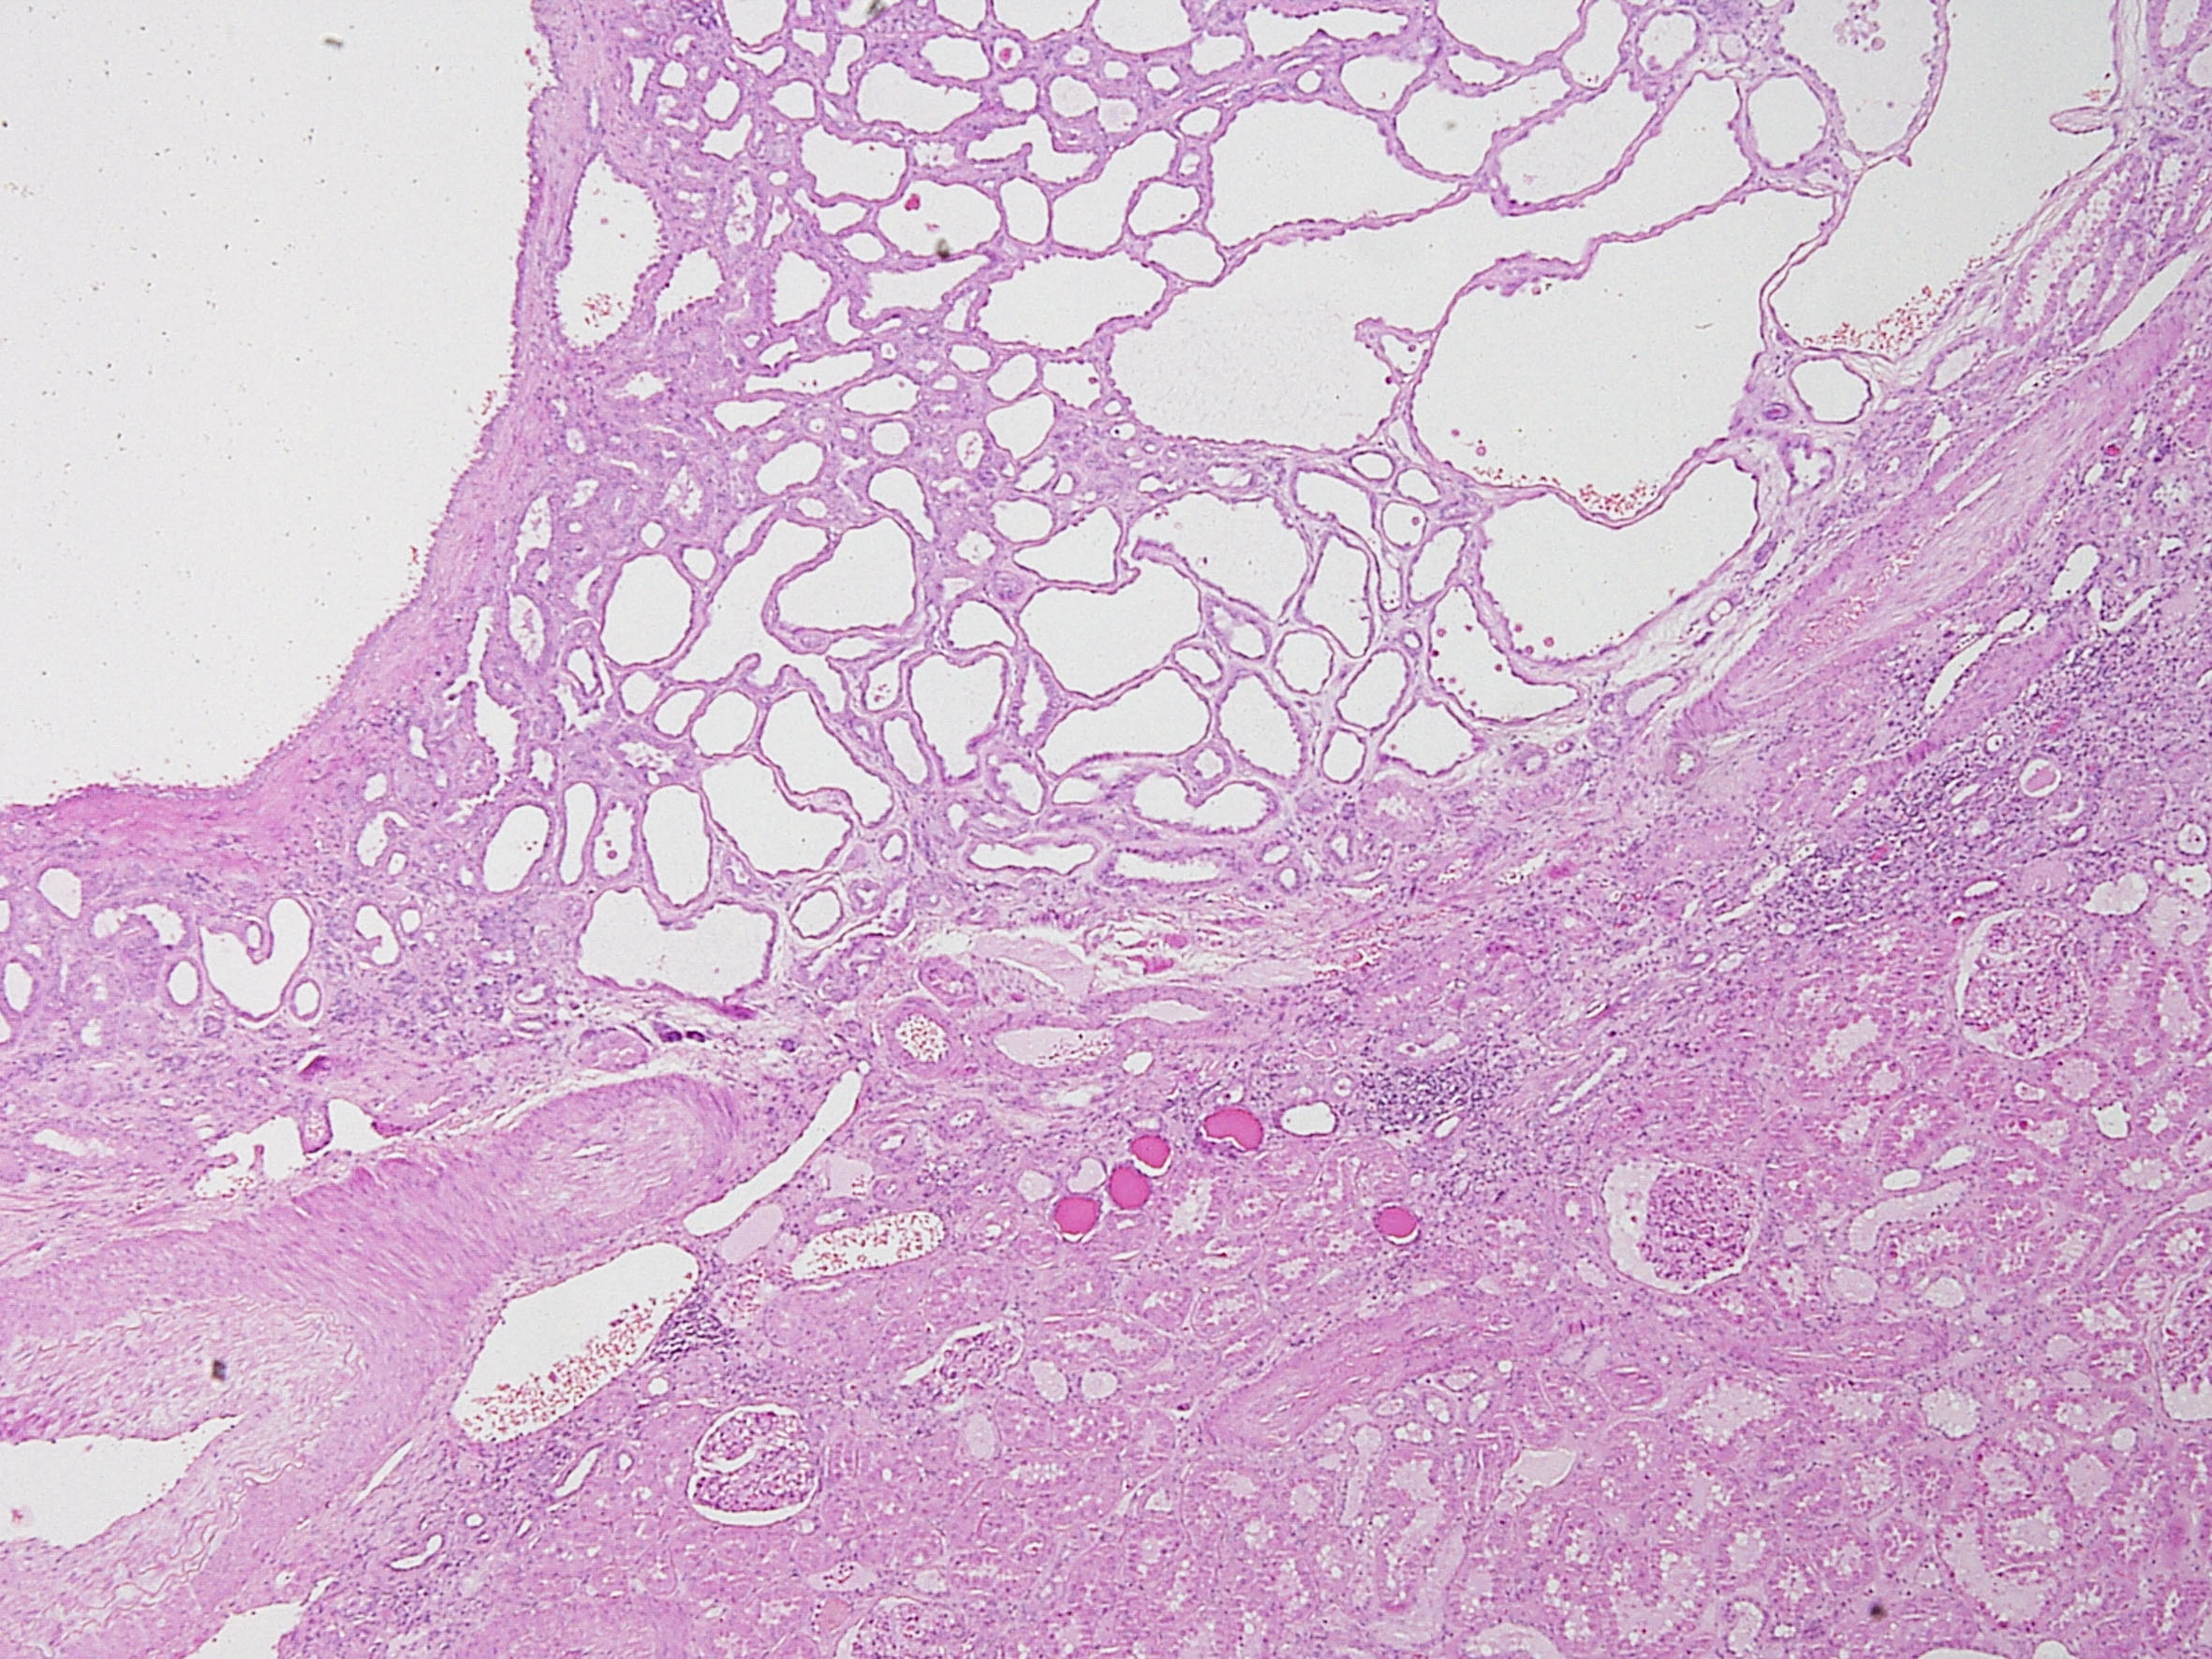

Consensus grade: Tubulocystic RCC

Tubulocystic renal cell carcinoma